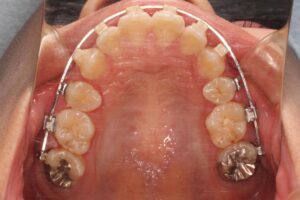

治療中の写真は外科手術直前に撮影したものです。初診時に比べて受け口が悪化したようにも見えますが、先ほど申し上げたようにこれは手術による顔貌の改善をはかるために敢えてそうしています。